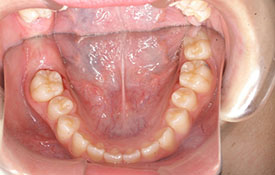

インビザラインの治療例:CASE-1

| プロフィール | 42歳 女性 |

| 所見 | 他院で行われた矯正歯科治療後の後戻りに悩まれて来院されました。 アイライナーの装着は、1日平均20時間ほどでした。 |